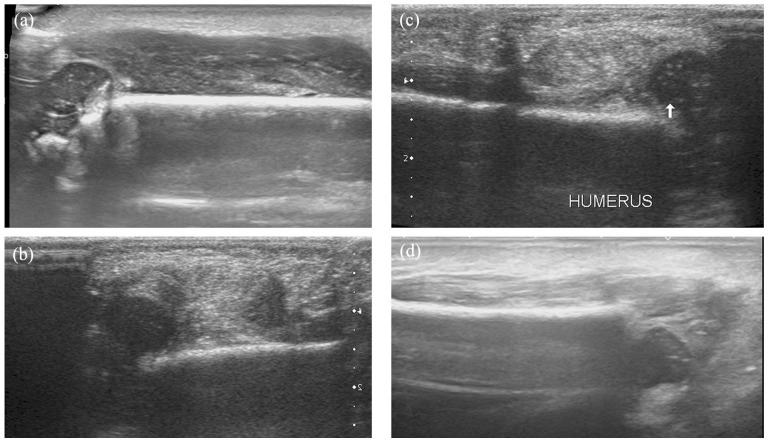

Methods: All consecutive infants treated between 2005 and 2020 for a transphyseal fracture of the distal humerus before the age of 6 months were retrospectively included. All radiological examinations were analyzed (X-ray, ultrasound, and magnetic resonance imaging (MRI)) as well as the therapeutic management (orthopedic or surgical treatment). The patients were seen at outpatient clinic visits with a minimum of 2-year follow-up.

Results: Nine newborns were treated. The main cause was an obstetrical traumatism (n = 8). The diagnosis was made on physical examination and addressed by obstetric departments with standard biplanar radiographs in four cases. The fracture was suspected on physical examination in the remaining five cases and confirmed by complementary imaging (ultrasound (2), MRI (1), and both (3)). A total of six patients were treated conservatively and three surgically with an open reduction. At a mean follow-up of 79 months, two complications occurred: one axillary abscess due to the cast and one cubitus varus deformity. All children had a full functional recovery.